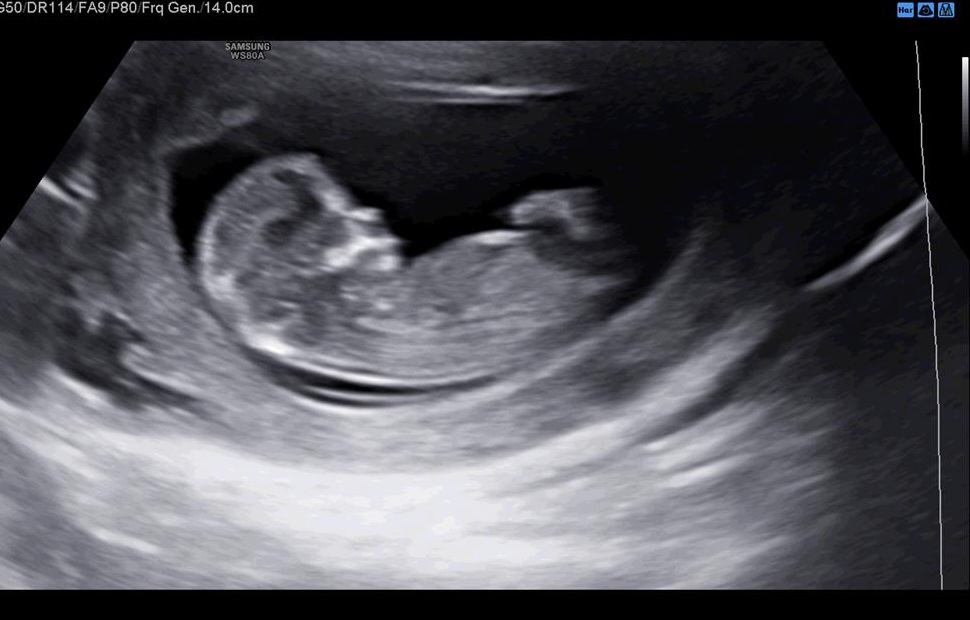

مامی_f69 عضویت: 1402/05/29 تعداد پست: 227 با توجه به عکس صفحه اول من فک میکنم دختره ولی اون استخونه دنبالچه خیلی معلوم نیست انشاالله که سالم ... میشه واسه منم بگی😔

گندمکوچولو عضویت: 1399/06/12 تعداد پست: 716 ای جونم انشاالله پسره و سالم من حالا برعکس دوست داشتیم دختر باشه ولی تو ان تی گفت پسره عزیزم این عکس ب دختر می خوره یا پسر 《یا کاشف الکرب عن وجه الحسین اکشف لی کربی بحق اخیک الحسین》یا ابا الغوث ادرکنی.💚

yasijoon90 عضویت: 1401/06/14 تعداد پست: 46 با توجه به عکس صفحه اول من فک میکنم دخترهولی اون استخونه دنبالچه خیلی معلوم نیستانشاالله که سالم و خ ... سلام میتونی واسه من تشخیص بدی